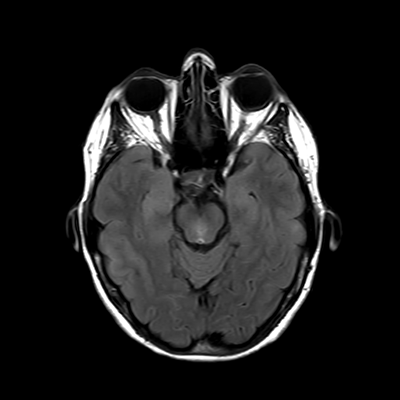

You also obtain an MRI of his brain once it's clinically safe to do so.

MRI brain (FLAIR)